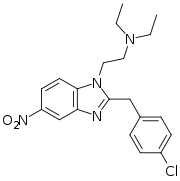

Benzimidazoles

Benzimidazoles opioids are also known as nitazenes.

- Metodesnitazene (Metazene)

- Etodesnitazene (Etazene)

- Metonitazene

- Etonitazene

- Etonitazepyne

- Etonitazepipne

- Isotonitazene

- Clonitazene